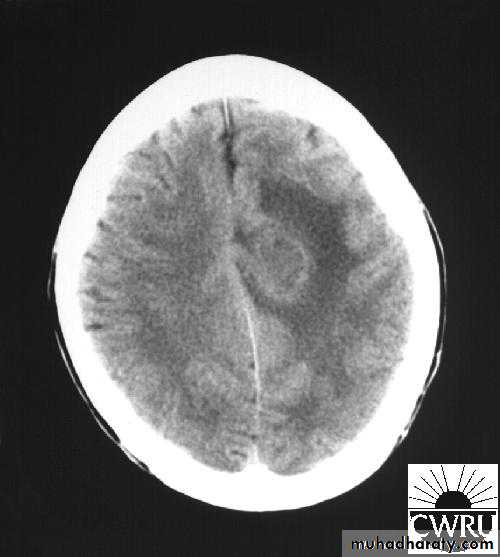

Brain Abscess CT without contrast

Neurosurgery

• They will show a single (or multiple) space occupying lesion that is well delineated with an enhancing wall, with variable surrounding oedema.

• The differential diagnosis of a single brain abscess in CT or MRI is a solitary metastasis, primary brain tumour or cerebral infarction.